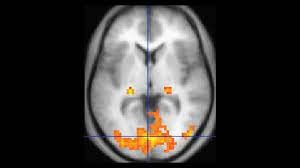

وطبقا للتقرير الصحفي الذي نشره موقع "ساينس ألرت" (Science Alert)، فقد قام الباحثون بقياس نشاط الدماغ لـ100 شخص مختلفين باستخدام التصوير بالرنين المغناطيسي الوظيفي (Functional magnetic resonance imaging).

ومن ثم، حَوَّل الباحثون نتائج التصوير السابق إلى مخططات رسومية ملونة، وذلك لبناء أطلس يشمل 419 نقطة في أدمغتنا؛ إذ يشير عالم الأعصاب المشارك في الدراسة إنريكو أميكو إلى أن "جميع المعلومات التي نحتاجها موجودة في هذه الرسوم، التي تعرف باسم الشبكة الكلية لوصلات الدماغ الوظيفية (Functional brain connectomes)".

وتعد شبكة وصلات الدماغ خريطةً عصبية لجميع الاتصالات التي تربط خلايا الدماغ، إذ يخبرنا فحص هذه الاتصالات -بواسطة الرنين المغناطيسي- بما يقوم به الأشخاص الخاضعين لعملية التصوير تلك، وتتغير أنماط هذه الاتصالات العصبية بناءً على النشاط الذي يقوم به الفرد، وذلك إثر تغير النشاط العصبي بين أجزاء الدماغ المُشترِكة في إتمام هذا النشاط أو ذاك.